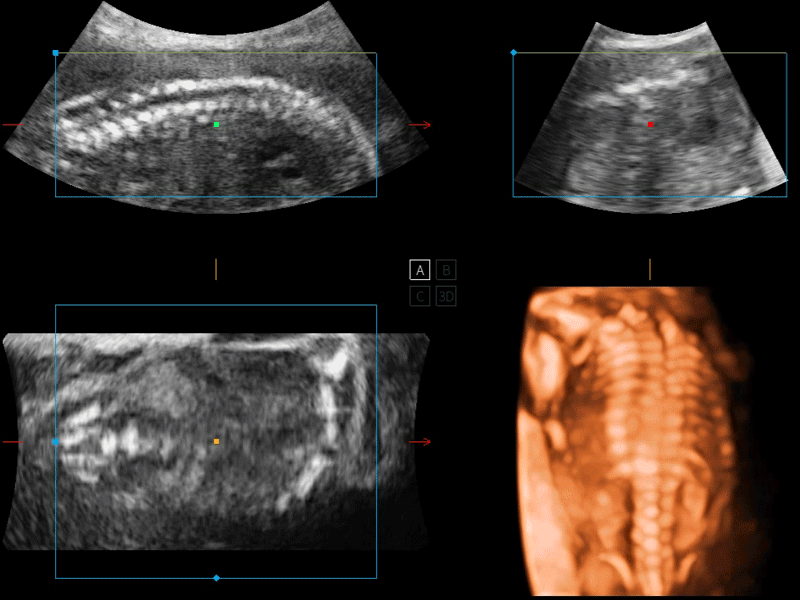

開立醫(yī)療通過不斷的技術(shù)創(chuàng)新,為大眾的生命健康提供持續(xù)關(guān)愛。P12 Plus采用全新一代超聲成像平臺(tái),新平臺(tái)旨在將真實(shí)還原組織解剖結(jié)構(gòu)作為首要目標(biāo)。平臺(tái)采用全新集成化硬件模塊,搭載新一代芯片,系統(tǒng)性能得到大幅提升,為您的診斷提供了豐富的臨床信息。優(yōu)異的圖像表現(xiàn),豐富的探頭配置,全面的應(yīng)用功能,為您日常診斷提供了可靠的助手。

彩色多普勒超聲診斷系統(tǒng)